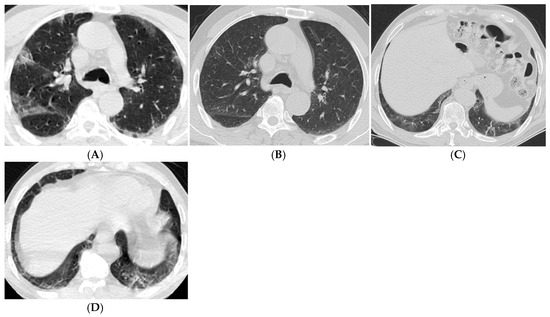

| Imaging Findings (>12 Months) | Common Findings | Persistent fibrotic changes, cysts, ground-glass opacities |